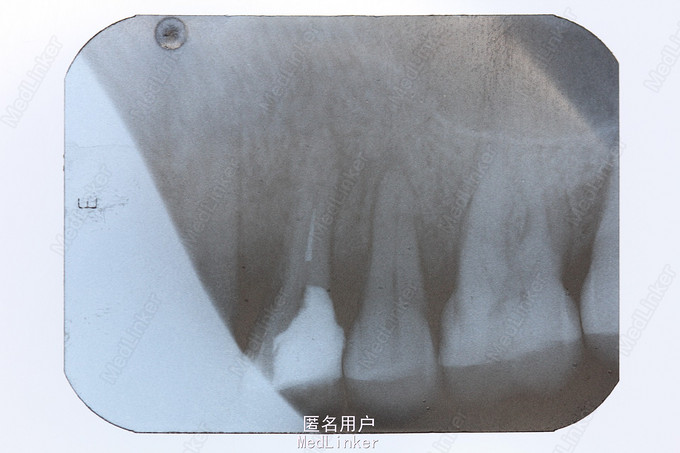

患者男,3日前于外院行根管治疗过程中遇器械分离,要求取出。

扩大根管上段通道,利用P5+ET25+橡皮樟,在显微镜直视下,从器械断端的颊舌向分别去除牙本质,解除器械卡死,取出分离器械。